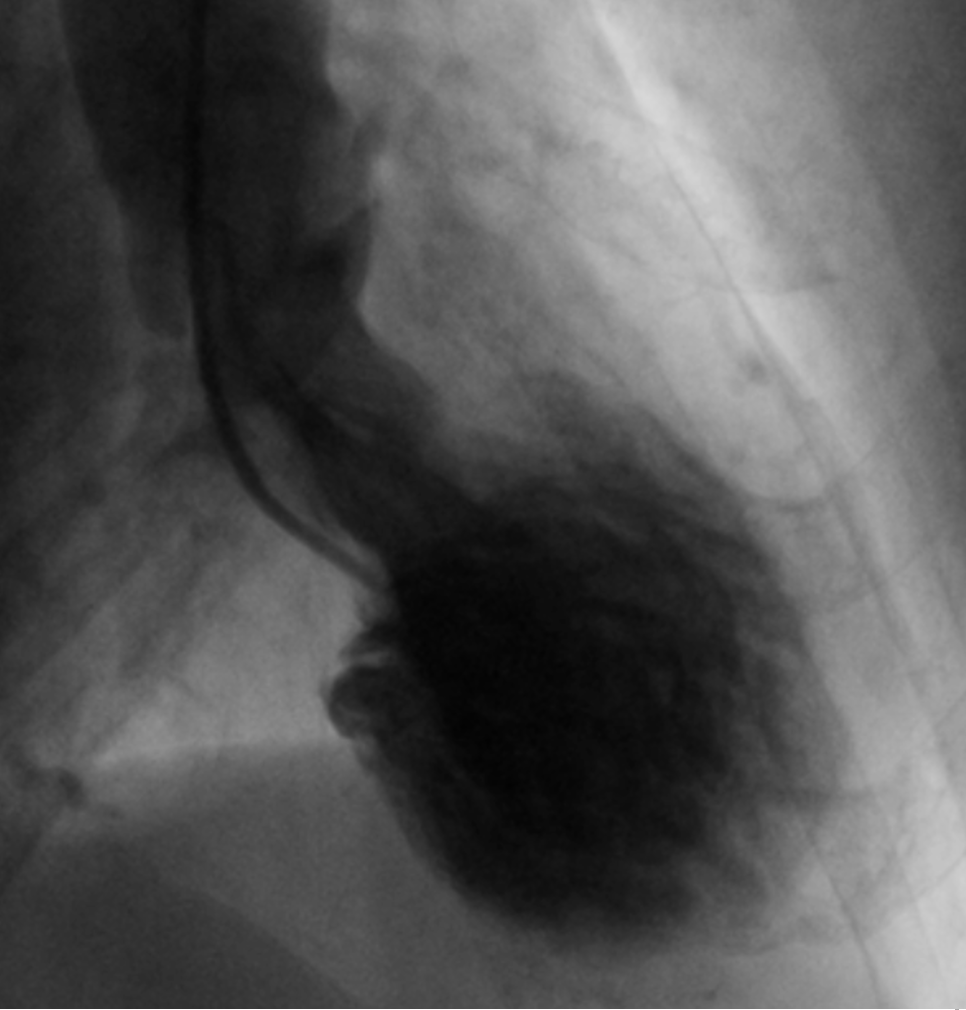

LVgram in diastole: